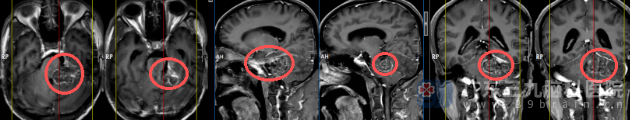

术前头颅MR检查提示:1.左侧桥小脑角区占位性病变,考虑软骨或骨来源病变可能,结合病史考虑骨瘤复发大小约34mm×49mm×34mm。

- 左侧桥小脑角区存在占位性病变,考虑为骨瘤复发并可能恶性变

- 病变紧邻脑干、面神经等关键神经血管结构